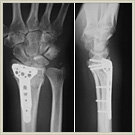

橈骨遠位端骨折:

転倒などにより手を着いた時に生じる頻度の高い手関節の骨折です。閉経後女性に多いですが、若い人でも強い外力が加わると骨折します。手術は、プレートと螺子を用いて骨をできるだけしっかりと固定します(ロッキングプレート)。当院では骨折の形態によってプレートを掌側もしくは背側に使い分けて設置しており良好な成績を得ています。